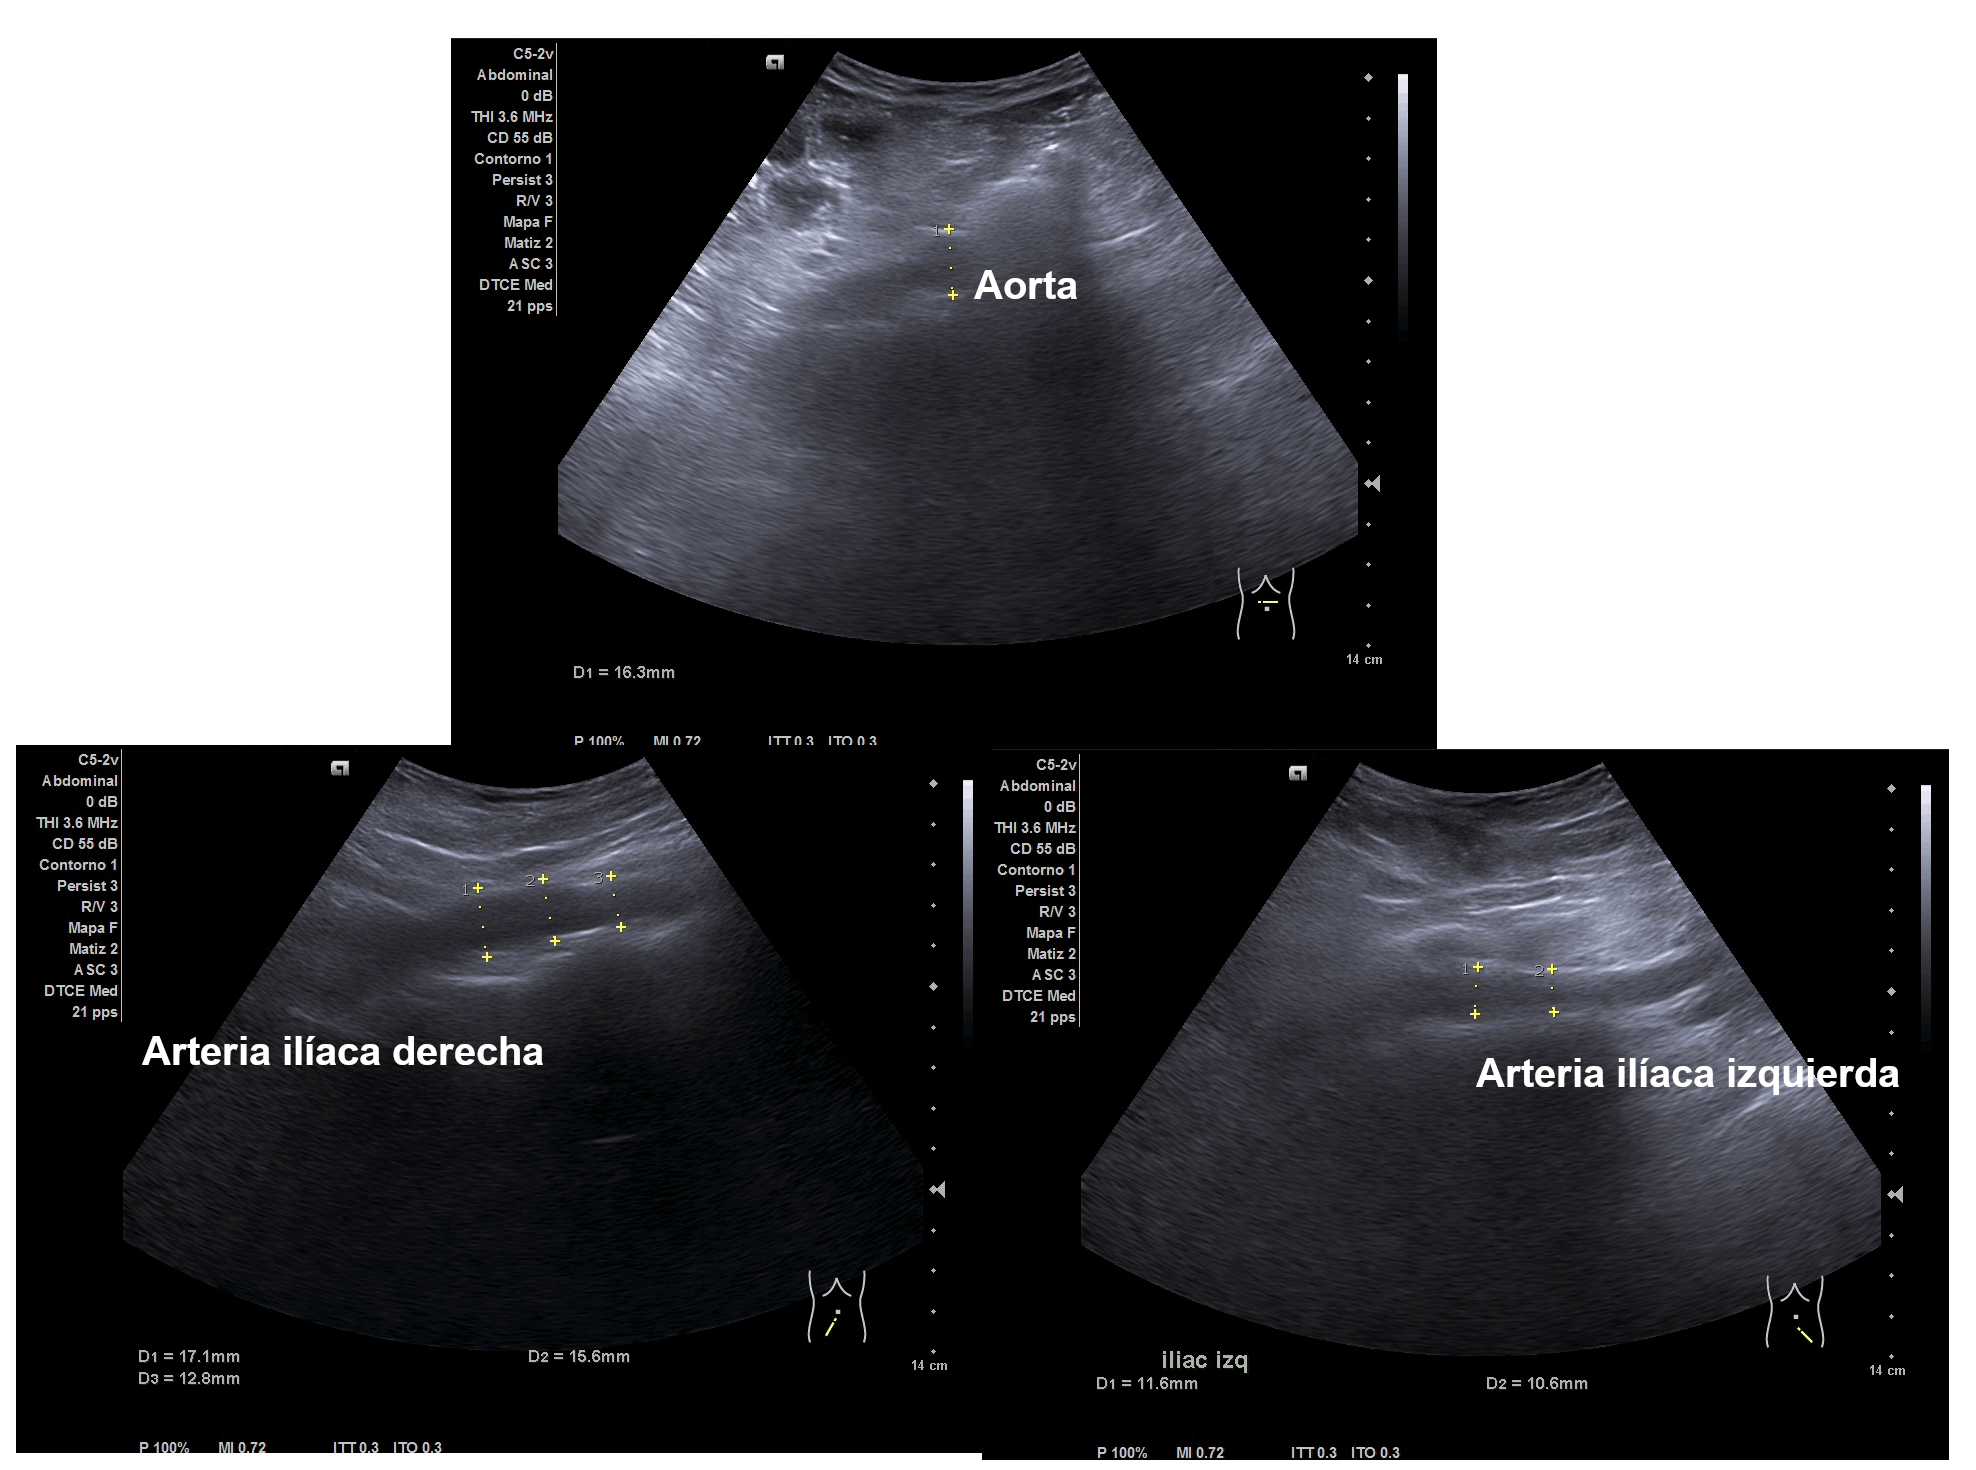

Parenquima hepatico sin alteraciones, vesícula biliar sin imagenes hiperecoénicas en interior. Pancreas visible en parte, sin alteraciones. Asimetría entre ambos riñones compatible variante de la normalidad RI. Llama la atención dilatación ilíaca derecha al comparar con contralateral y con aorta abdominal distal. Compatible con dilatación aneurismática ilíaca derecha.

El diagnóstico diferencial del Aneurisma Ilíaca con: Displasia fibromuscular u otra patología del tejido conectivo, lúes o tuberculosis entre otros. Toda dilatación que sobrepase el 50% del diámetro del vaso se considera aneurismática. Por la edad no se plantea el origen ateromatoso.

La ecografía en Atención Primaria se plantea en el contexto de responder a una pregunta clínica tras la anamnesis y la exploración física u otras pruebas complementarias que se precisen. A resaltar, la importancia de realizar ecografía completa siguiendo una sistemática y prestando atención tanto a variantes de la normalidad como a hallazgos patológicos. En el caso de la ecografía abdominal, es fundamental explorar los grandes vasos tanto en plano transversal como longitudinal, haciendo incapié en la división de las ilíacas.